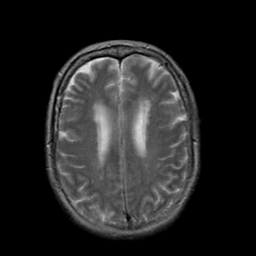

The main limitation of the above-mentioned methods is their dependency on a large number of paired images, i.e., both images belong to the same patient, perfectly registered for training [27], which is difficult to obtain. If the registration has a local mismatch between different modalities, the learning models would generate irrelevant images. To overcome this issue, Zhu et al. [49] proposed cycleGAN to synthesize images from unpaired data in an unsupervised manner. Although cycleGAN has shown remarkable results in reconstructing identical images to the real input, e.g. CT-to-CT, it can not be directly used to synthesize samples from another modality, e.g., MR-to-CT, as there are no direct constraints between real source and synthetic images [39]. For example, Zhang et al. [46] alleviated this issue using an additional loss to force the generated images to be the same as the real ones. Later, SC-cycleGAN [39] defined a structure-consistency loss into the cycleGAN. Specifically, modality-independent neighborhood descriptor (MIND) [9] and a position-based selection strategy is used as structural features and slice selection, respectively. Moreover, several studies conducted bidirectional prediction, i.e., synthesis of CT images from given MR images and vice versa [38, 1]. In addition, many cycleGAN-based methods have been proposed for medical image synthesis from unpaired data [10, 29, 3], but these methods only used the basic discriminator. The basic discriminator only utilizes images in the target domain, while we discovered that using reference images from only the target domain leads to a problem, as shown in Fig. 1 and 2.

In this paper, we propose a bidirectional learning model, known as dual contrast cycleGAN (DC-cycleGAN), for medical image synthesis from unpaired data. Specifically, a dual contrast (DC) loss is formulated that leverages the advantage of samples from the source domain as negative samples to indirectly build constraints between real source and synthetic images via discriminators, and synthesize images more related to the target domain by enforcing the synthetic images to fall far away from the source domain. In addition, structural similarity index (SSIM) [35] and cross-entropy (CE) [48] are integrated into the DC-cycleGAN structure to avoid disappearing gradient information that is caused by a mean absolute error (MAE) and synthesizing irrelevant images. SSIM considers luminance [35] and CE converges fast as its back-propagation error is less than MSE [28]. As can be seen in Figs. 1 and 2, using SSIM and CE with dual contrast can generate more clear and accurate MR images as compared with that of MAE and MSE, and SSIM and CE without dual contrast loss. Although both SSIM and CE with dual contrast and without dual contrast generate similar CT images, SSIM and CE with dual contrast quantitatively generate better images as shown in Table 4. The experimental results indicate that DC-cycleGAN is able to consider more complex features such as structure in synthesizing images and produce remarkable results as compared with other state-of-the-art methods reported in the literature.

Tables 3 and 4 show the results of MR and CT synthesis, respectively. As can be seen, all components play vital role in both tables. SSIM & CE (w) performs significantly better than other losses in synthesizing MR images. This also can be seen visually in Fig. 1. In contrast, SSIM&CE (w) performs slightly better than SSIM&CE (wo) in synthesizing CT images, both generate more or less similar CT images (see Table 4).